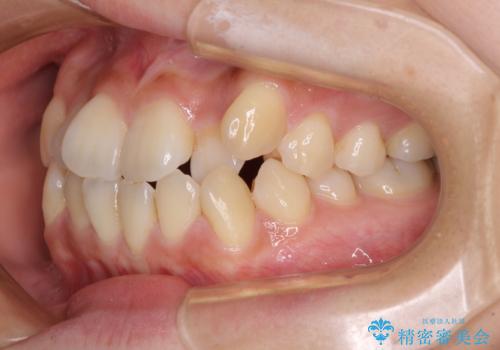

- 八重歯や前歯の捻転とクロスバイトが気になり、インビザラインによる矯正治療を希望して来院された患者様です。

上顎側切歯(上の真ん中から2番目の歯)が舌側転位している場合、無理して動かそうとすると歯髄壊死を起こすリスクが高い印象があります。

インビザライン単体でも治療は可能ですが、安全策としてインビザラインで歯列を移動する前に上顎前歯をワイヤー矯正で整え、その後上下歯列をインビザラインにて矯正治療を行うこととしました。

舌側転位している側切歯特有の、切縁の位置が不揃いであったり、根元が内側に引っ込んだ状態であったりという、インビザライン独特の仕上がりになることなく、きれいに整った歯列とすることができました。